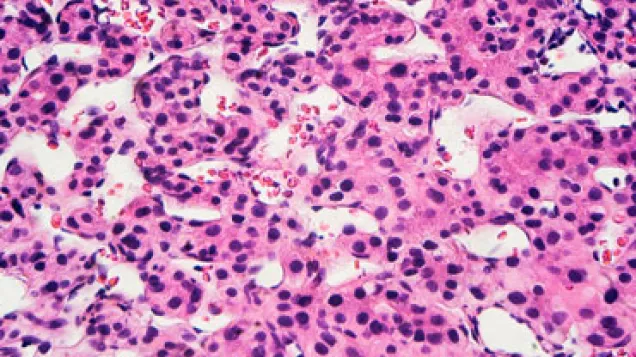

Viral hepatitis affects millions of people across Europe but as many infections are accompanied by no symptoms, the ‘silent disease’ is often not diagnosed. Left untreated, chronic infection with hepatitis B and C may progress to liver cirrhosis or cancer.

Around 4.5 million people are estimated to suffer from infection with hepatitis B and some 5.5 million from hepatitis C infection in the EU – and the majority of these individuals are unaware of their infection. Untreated chronic hepatitis B and C infections may lead to liver cirrhosis or cancer.